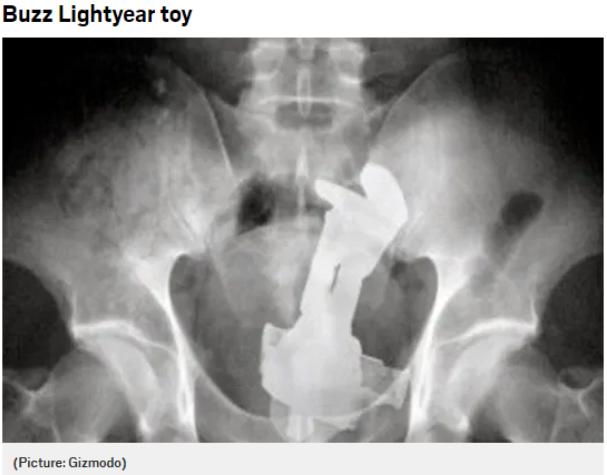

人们都在菊花里塞了什么东西?就挺离谱的

世界之大,无奇不有。本来以为这世界已经够“有趣”了,但是当我第一次看到这张时,还是在毫无准备的情况下有被人类的“迷惑行为”震惊到。